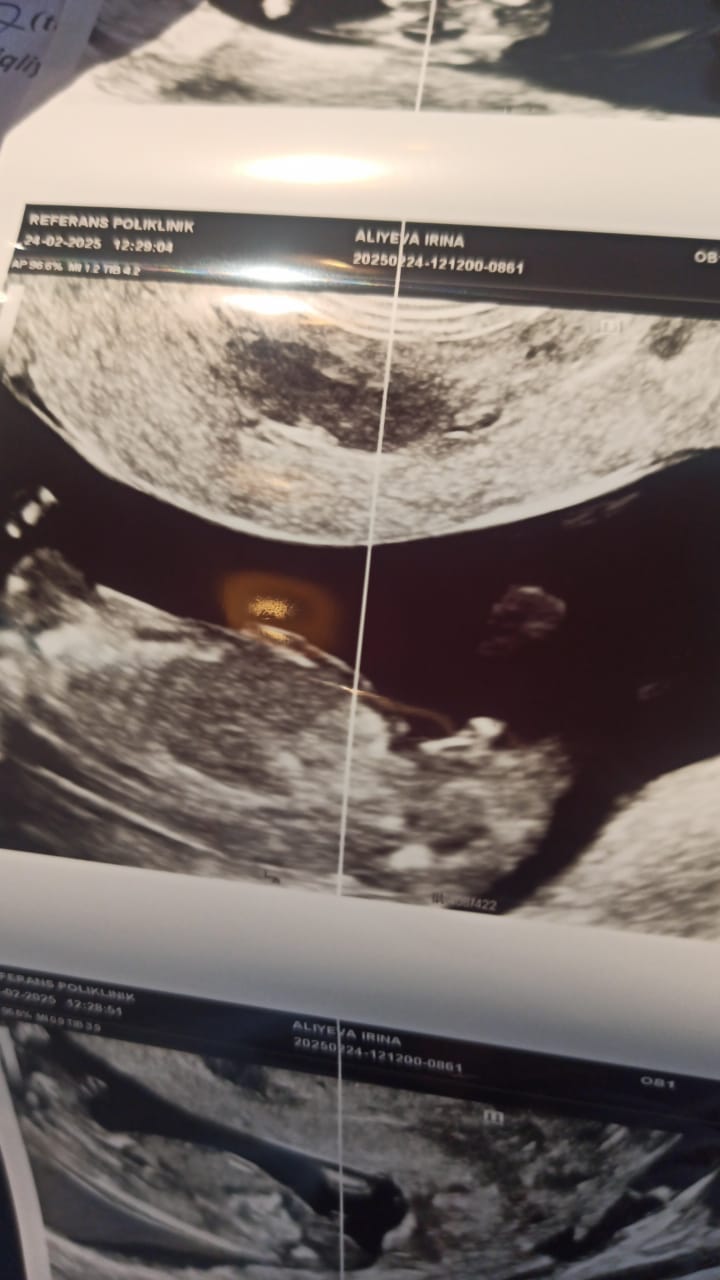

Мальчик или девочка?? 12 недель 4 дня

Общим консилиумом 7ых Узистов + 3 врача Решили и твёрдо поставили жирную точку- у нас будет мальчик. Клиника также провела УЗИ обследование, их врач по размеру плода определили что уже 13 недель и 4 дня и сами чётко увидели , что у девочки такого клитора быть не может...говорят крупный и хорошо развивающий плод Итог: клиника принесла извинения и готова за эту цену сделать нам расширенный НИПТ, но я им уже не доверяю, и забрала свои денежки обратно. Изображение Изображение